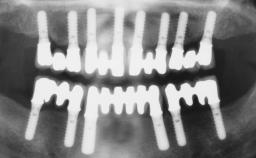

Conventional Loading of Six Implants in the Mandible and Final Restoration with a Full-Arch Metal-Ceramic FDP

A 68-year-old, completely edentulous male patient presented for evaluation and treatment options. He reported excellent general health and was taking no regular medication. He had been edentulous for approximately 12 years, having lost his teeth to periodontal disease and dental caries. The patient’s chief complaint was incompetent function. His secondary concerns included his appearance and the desire for a predictable outcome. He attributed his reduced functional capacity to his lower complete denture, which he described as poor. He was particularly concerned with the denture’s instability and poor fit. In general terms, he was satisfied with the maxillary complete prosthesis. The maxillary prosthesis was characterized by adequate retention, stability, and support, although the fit was considered less than ideal.